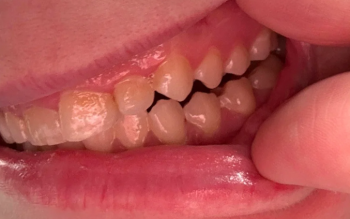

| Aesthetics | The goal is to restore the natural contour of the tooth for an optimal smile. | Limited. Only suitable for the smallest, most superficial chips. It will shorten the tooth and may look uneven. | Excellent. Restores the missing tooth structure, allowing the dentist to match the tooth's original size, shape, and color. |

| Sensitivity | A chip/fracture may expose the underlying dentin, causing sensitivity to hot/cold/air. | Ineffective. It does not cover exposed dentin and may even increase surface sensitivity by exposing more dentin. | Effective. The resin material seals the exposed area, instantly insulating the dentin and nerve, reducing or eliminating sensitivity. |

Treatment: Given the visual chip and the fracture line, Dental Bonding is the superior, more conservative treatment over smoothing.

The dentist will etch the tooth, apply a composite resin matched to your tooth color, sculpt it to restore the lost corner and cover the fracture line, and cure it with a special light. This is typically done in one appointment (30-60 minutes).